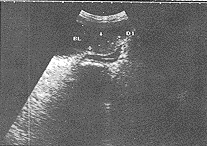

BL:膀胱,箭头所指为膀胱颈部实性结节,DI:结节测值32.4mm

图1 女性前列腺病

中国超声医学杂志990644 患者女,71岁。于2年前无明显诱因出现尿频,夜尿增多,尿流变细、排尿费力呈滴沥状,无尿痛。曾多次就诊当地卫生院治疗,症状反复发作。于1月前上述症状加剧,伴下腹部胀痛,就诊本院。B超检查所见:双肾大小正常,左肾上部囊肿36mm×37mm,余实质回声均匀,集合系统未见异常。右肾未见异常。双输尿管无扩张。膀胱过度充盈,壁增厚5~7mm、粗糙,膀胱内未见结石。于膀胱颈部见实性等回声结节32mm×26mm×23mm,内回声均匀(图1)。B超诊断:1.膀胱颈部实性结节(女性前列腺病);2.尿潴留、膀胱壁增厚;3.左肾囊肿。行手术治疗,术中所见:膀胱明显增大:壁增厚,颈部抬高呈环状增厚,切开粘膜,钝性剥离膀胱颈部切除增厚组织。病理诊断:膀胱颈粘膜慢性炎症伴鳞状上皮增生,糜烂,病变累及浅肌层,浅肌层肌组织变性,伴结缔组织增生。